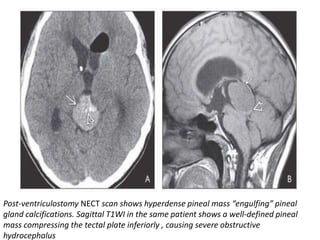

Post-ventriculostomy NECT scan shows hyperdense pineal mass “engulfing” pineal

gland calcifications. Sagittal T1WI in the same patient shows a well-defined pineal

mass compressing the tectal plate inferiorly , causing severe obstructive

hydrocephalus